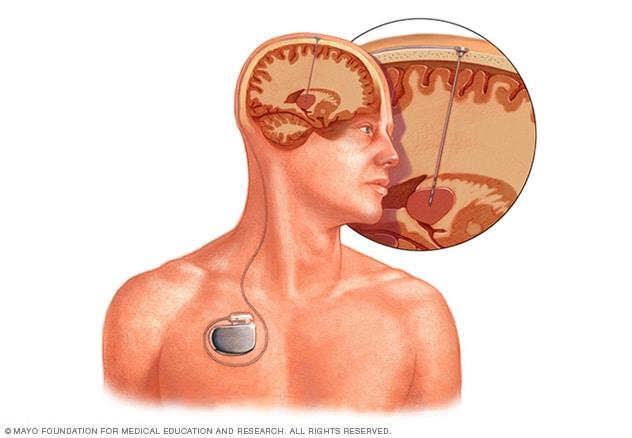

In vagus nerve stimulation, a device placed under the skin of the chest stimulates the vagus nerve in the neck. This sends signals to the brain that lessen seizures.

Deep brain stimulation involves putting electrodes deep within the brain. The impulses from the electrodes help the body manage the brain activity that causes seizures. The electrodes attach to a pacemakerlike device placed under the skin of the chest. The device manages how much stimulation happens.